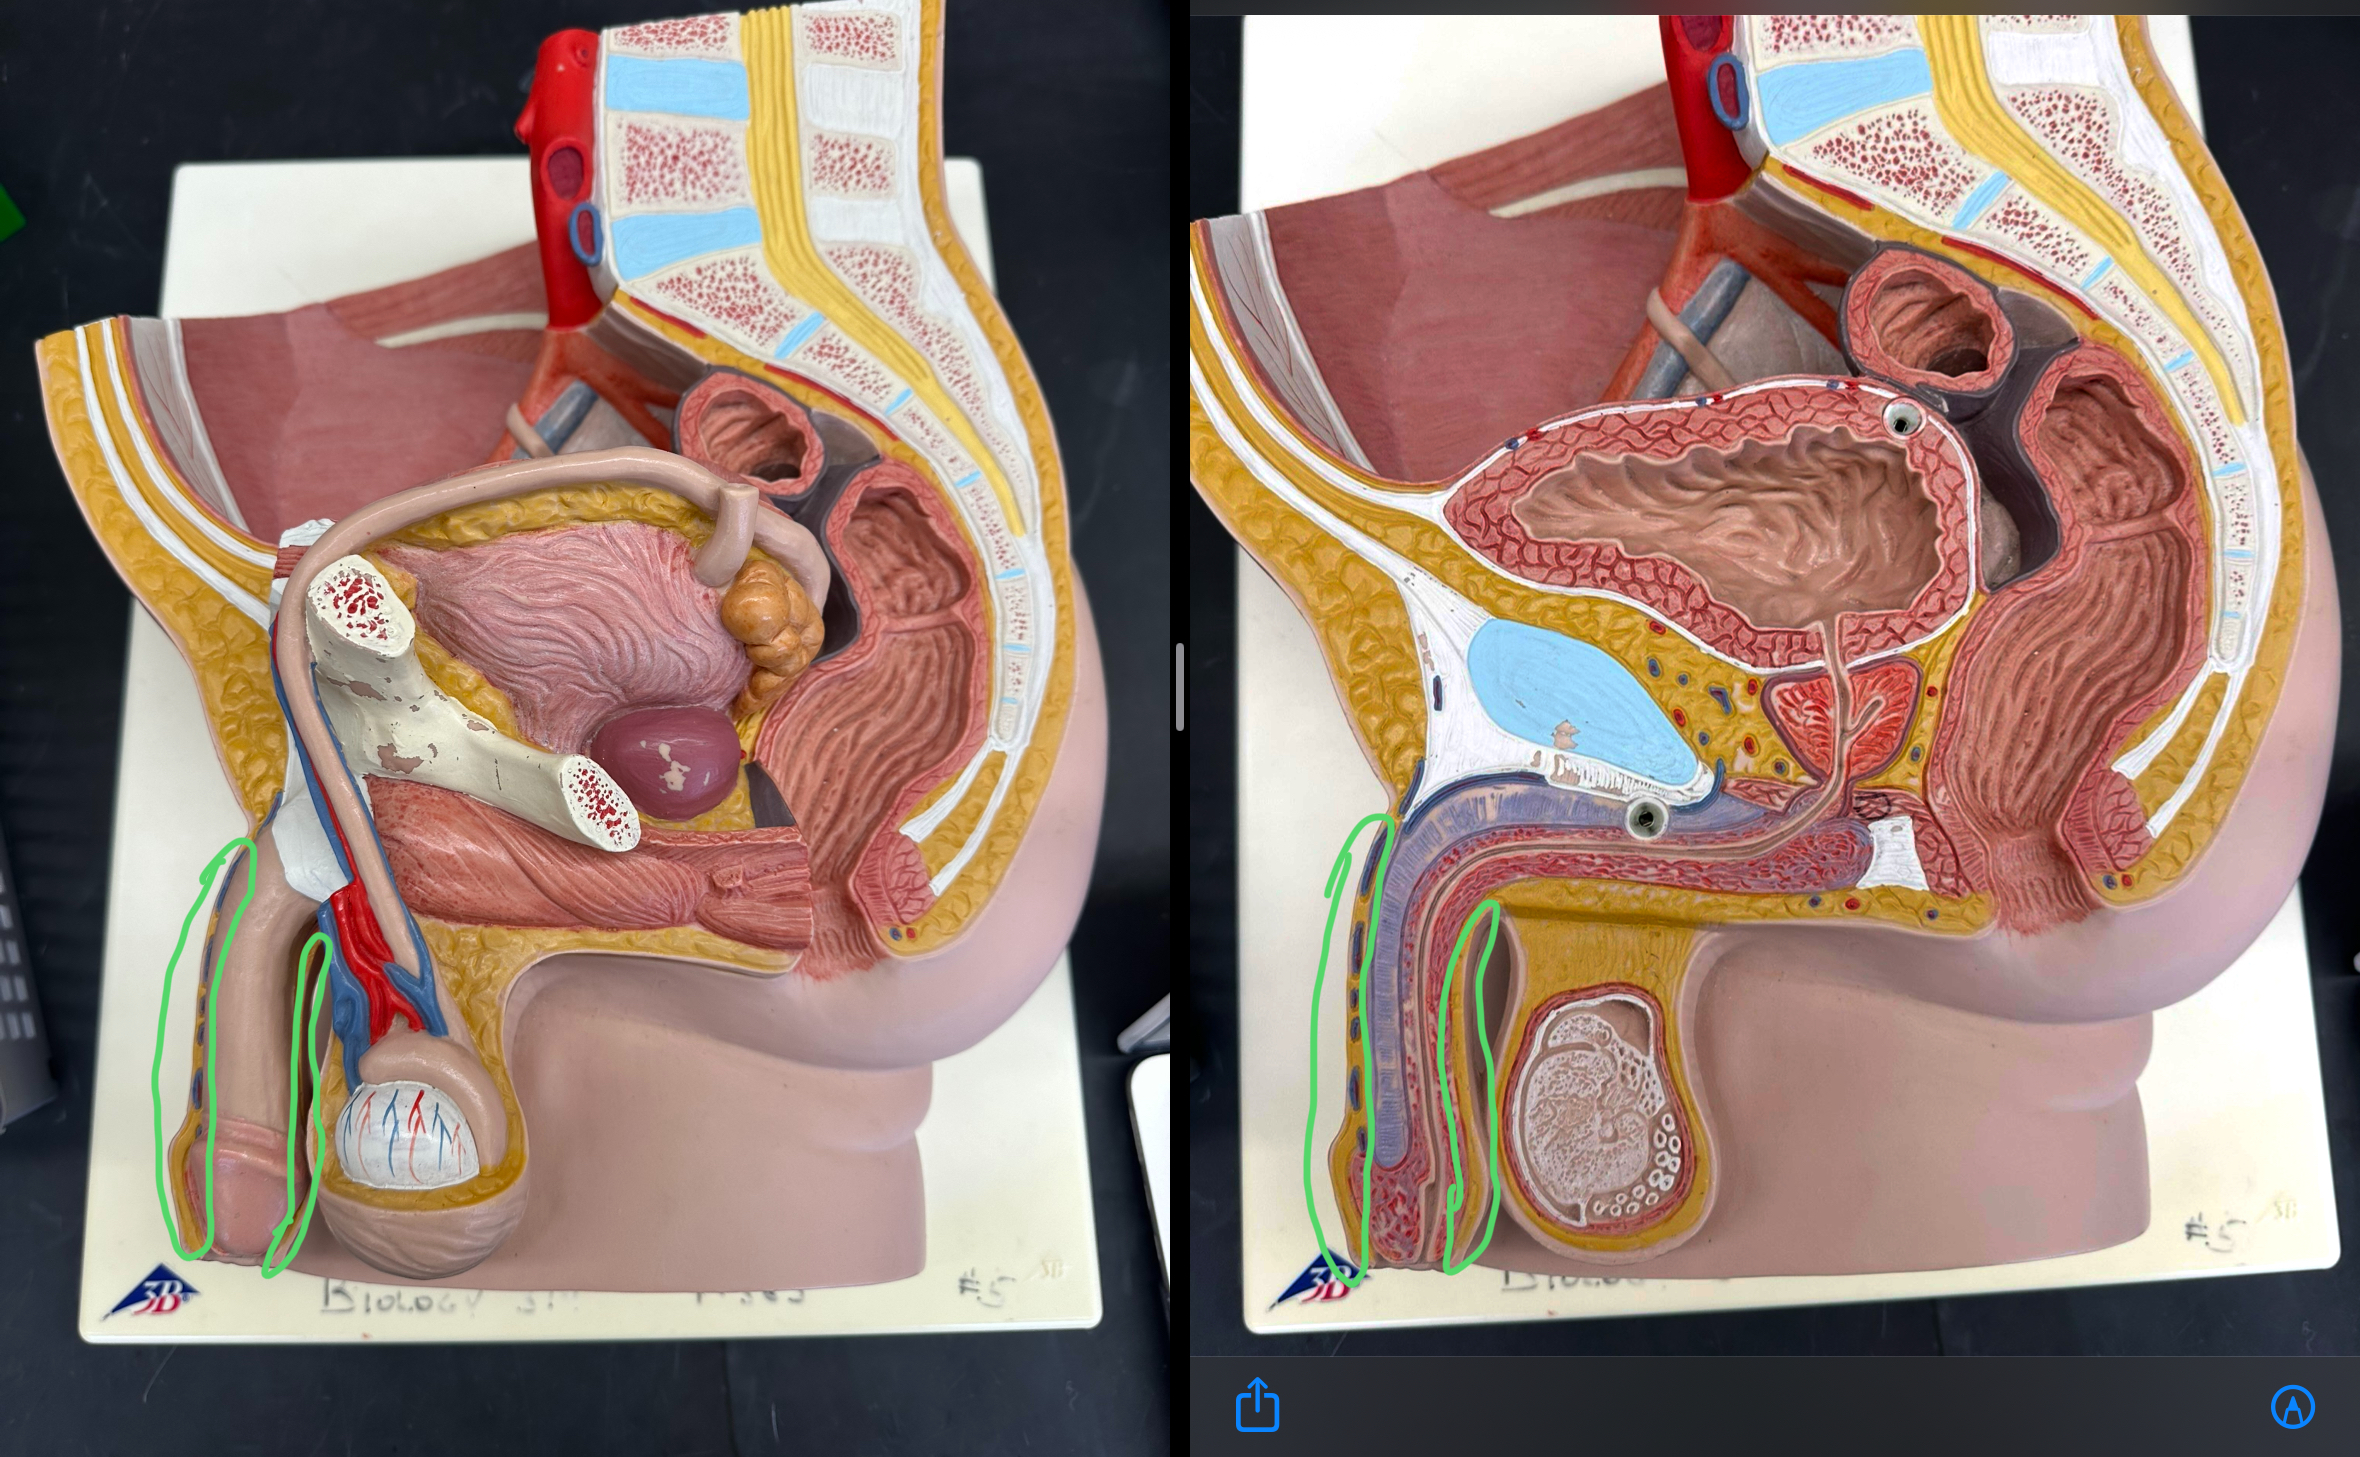

scrotum

testis

tunica albuginea

tunica vaginalis

seminiferous tubule

lobule

septum

rete testis

efferent ductule

all parts

epididymis

head

of epididymis

body

tail

spermatic cord

ductus deferens

ampulla of ductus deferens

ejaculatory duct

seminal gland

prostate gland

bulbourethral gland

whole

urethra

prostatic urethra

membranous urethra

spongy urethra

juvenile penis

penis

post-pubescent penis

as a whole

erectile tissue

corpus cavernosum

corpus spongiosum

external urethral orifice

prepuce

glans penis